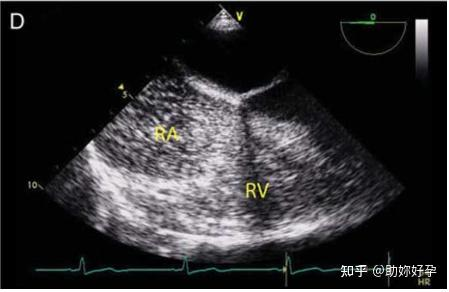

注射造影剂后,它们暂时停留在血液中,可以与心肌分开显示。之所以会出现这种现象,是因为气体中超声的阻抗与软组织中的明显不同。阻抗是密度和传播速度的乘积,空气中的阻抗较低,而软组织中的阻抗较高。当这种差异出现时,超声会被微泡强烈反射,从而提高对比度分辨率和感兴趣结构的可视化(图 13D)。